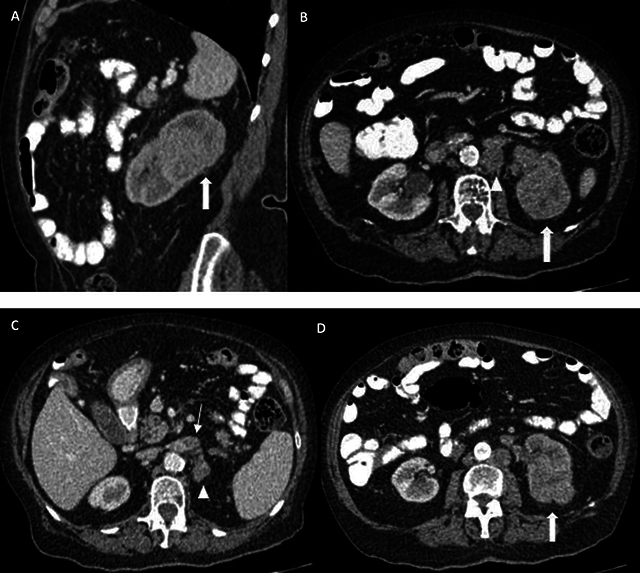

In hereditary leiomyomatosis and renal cell carcinoma syndrome, fumarate hydratase-deficient renal cell carcinomas typically present as aggressive, unilateral, often cystic masses with heterogeneous enhancement. These tumors can metastasize early, making appropriate imaging and staging critical for diagnosis and management. Teaching point: When a renal lesion suspected of RCC is identified in a patient with cutaneous and uterine leiomyomas, HLRCC should be evaluated, which is important for future genetic counseling.